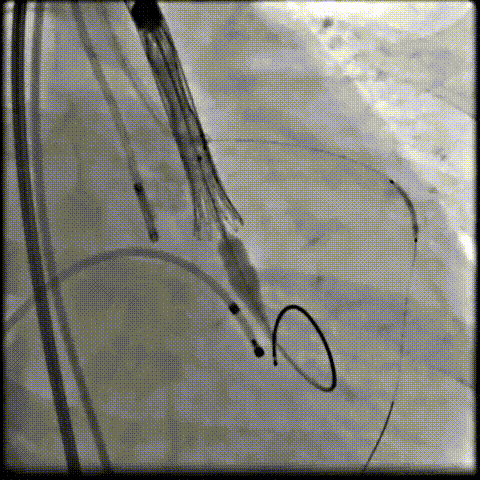

术中影像

根部造影可见返流,23mm球囊预扩张

无窦侧严重钙化及融合影响,

瓣膜(AV29)释放不稳出现反复上跳,2次回收尝试

重新定位释放,

钙化及融合挤压导致瓣膜(AV29)下滑位置偏深

第三次回收重新定位

工作位造影位置良好,完全脱钩释放瓣膜(AV29)

考虑支架腰部挤压,23mm球囊充分后扩后形态良好,

极微量瓣周漏